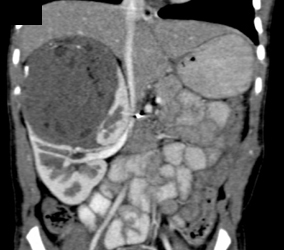

Wilms Tumor